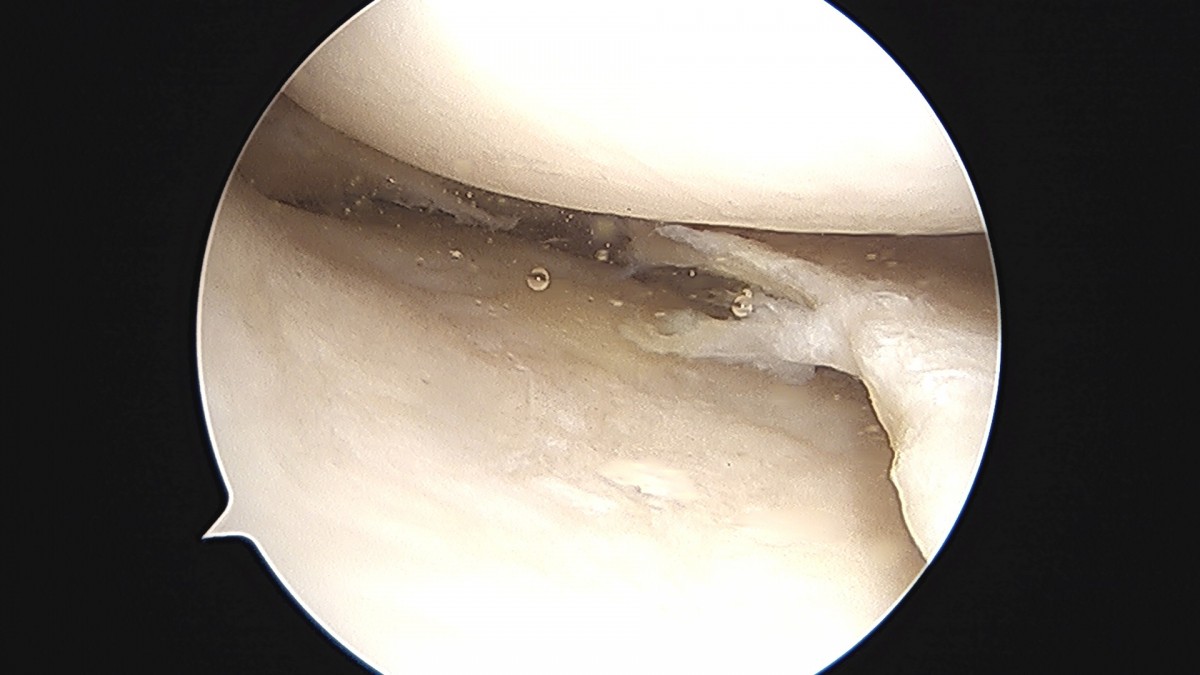

이재상원장님 무릎 반월상 연골판 절제술 강일O 환자

작성자 최고관리자 댓글 0건 조회 372회 작성일 25-09-16 16:12